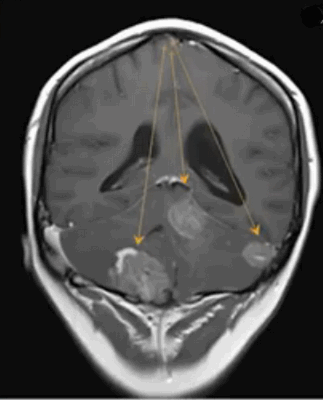

Опухоль мозжечка на МРТ (указана стрелкой)

Опухоли головного мозга долгое время диагностировали исключительно по клиническим признакам, часто слишком поздно. С появлением нейровизуализационных методов стало возможным выявление опасных патологий на ранних этапах их развития. Уже на первых стадиях формирования опухоль головного мозга на МРТ отчетливо видна, а врачи могут планировать дальнейшие действия. Ранняя диагностика увеличивает шансы на выздоровление даже при онкологических заболеваниях.

Метастазы в головном мозге на постконтрастном изображении (указаны стрелками)